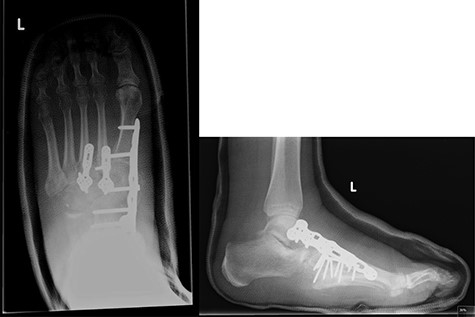

Post-operative X-rays (AP and lateral), demonstrating good reduction and fixation of fracture dislocations.

The patient was initially managed with a total contact leg cast, followed by open reduction and internal fixation (ORIF) with locking plates, combined with lengthening of the tendo-Achilles to permit full dorsiflexion and subsequent re-casting (Fig. 5). Her post-operative progress was satisfactory, and she is currently non-weight bearing for 6 months post-ORIF.